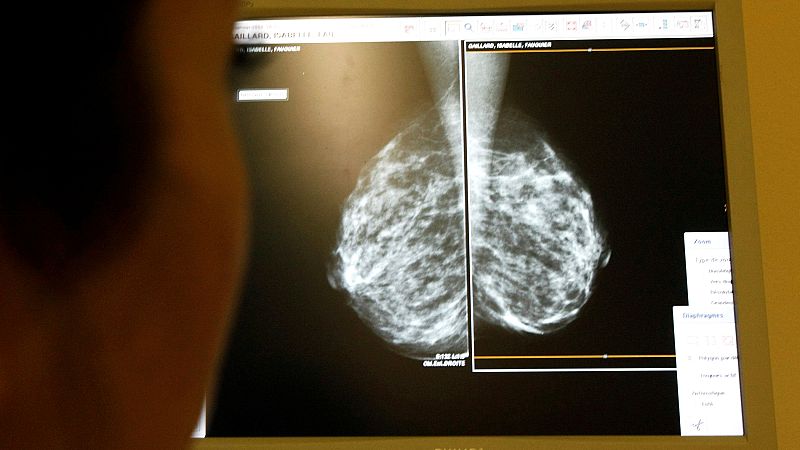

Ya son más de 200 las mujeres que van a presentar denuncias individuales por esta crisis de los cribados en Andalucía, según el abogado de la asociación de afectadas Amama.

A la espera de respuestas claras, el consejero de Sanidad andaluz, Antonio Sanz, señaló a los hospitales. "Creo que estamos ante una cuestión de autoorganización y modelo asistencial en algún hospital, o algunos hospitales, mucho más en uno, que llevó a una situación muy crítica", afirmó, una respuesta que no convence en Amama.

La ministra de Sanidad se reúne con Amama para abordar los fallos en los cribados de cáncer

La presidenta de la asociación, Ángela Clavero, se reunió esta semana también con la ministra de Sanidad, Mónica García, que les trasladó que están estudiando acciones legales y administrativas para que las comunidades gobernadas por el PP entreguen los datos de los programas de detección precoz.

García acusado a la Junta de Andalucía de haber "perdido el control" del sistema sanitario y calificó los fallos como una "negligencia estructural", una muestra de las posturas coincidentes de las partes del PSOE y Sumar en el Gobierno en esta cuestión.